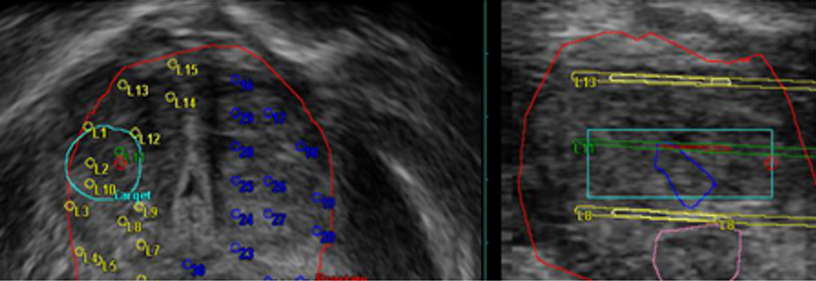

- Ultrason sisteminin bulunmadığı durumlarda bile, Workstation’ınıza yazılım yükleyerek MRI ve BT verilerinin kontur çıkarımı yapılabilir. Bu, biyopsi inceleme süresini azaltmaya yardımcı olacaktır.

- Biyopsi sonrası patolojik tanı sonuçlarını (Gleason Skoru) girmek ve aynı kullanıcı arayüzü ile raporlar oluşturmak mümkündür.

- Hem harici konturlama yazılımları hem de ARIETTA 65 IntuitiveFusion ile oluşturulan veriler, DICOM ve çeşitli medyalar aracılığıyla çift yönlü olarak aktarılabilir ve böylece Füzyon görüntüleme için optimum sonuçlar elde edilebilir.